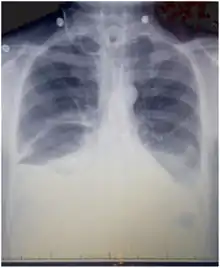

Chest X-rays can detect a chylothorax. It appears as a dense, homogenous area that obscures the costophrenic and cardiophrenic angles. Ultrasounds can also detect a chylothorax, which appears as an echoic region that is isodense with no septation or loculation. However, neither a normal chest x-ray nor an ultrasound can differentiate a chylothorax from any other type of pleural effusion.[1]